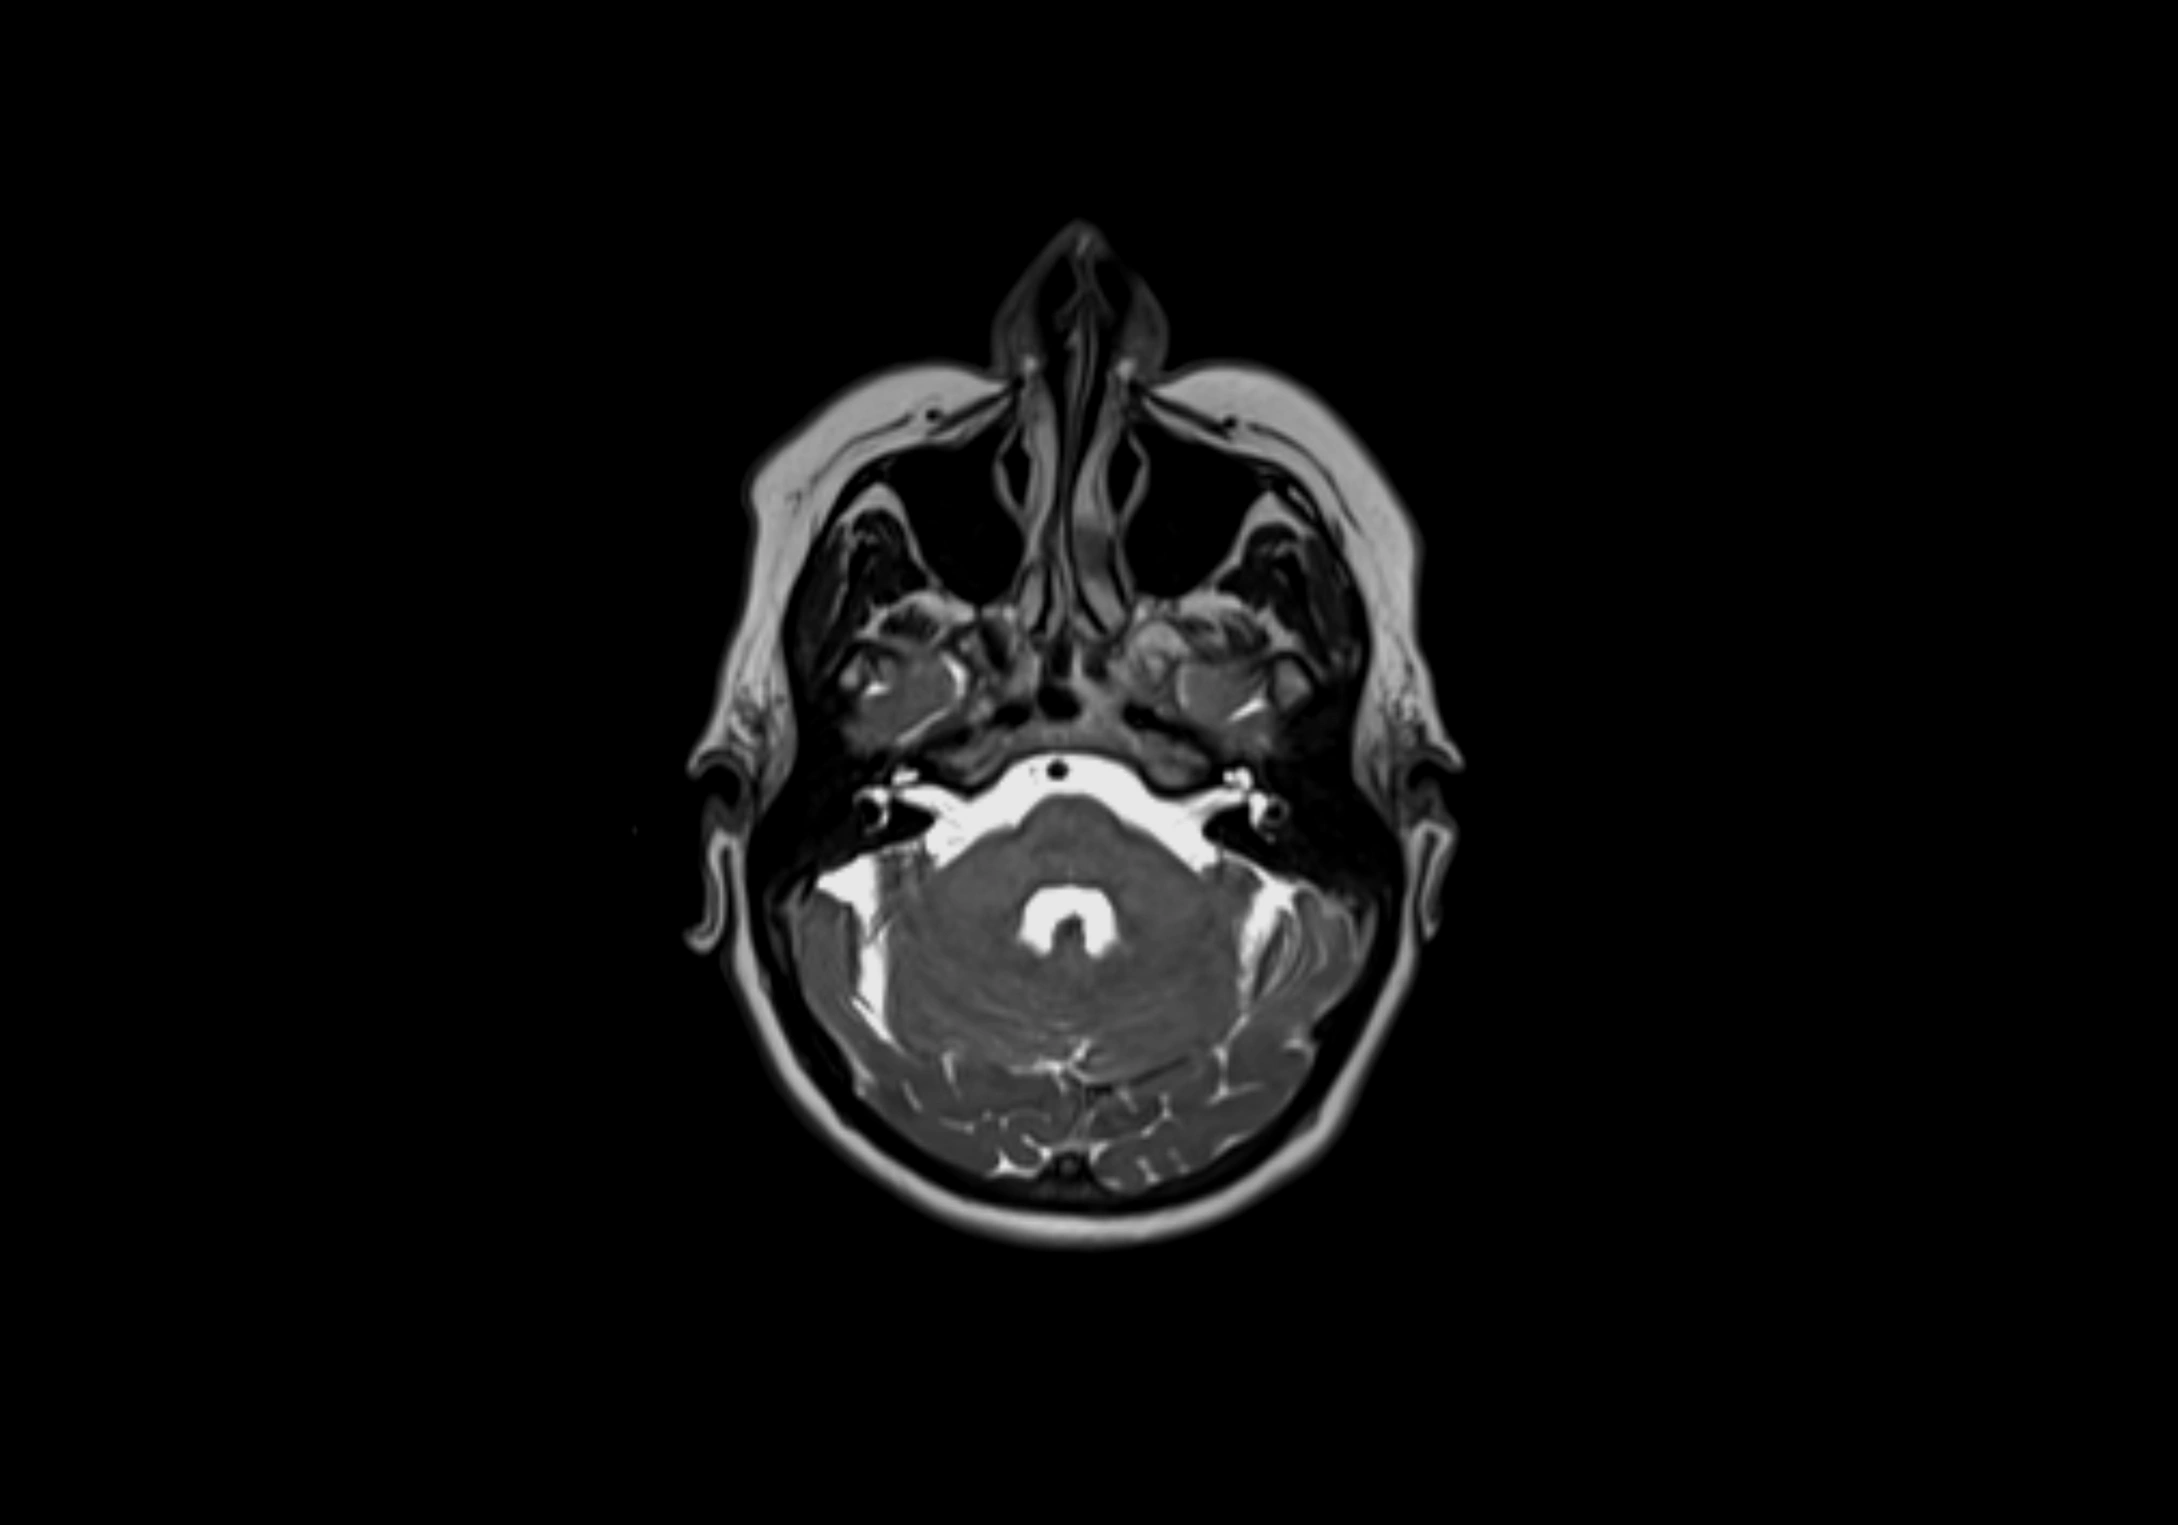

MRI Appearance

T2-weighted images:

• Nodes show intermediate signal, with surrounding fat bright

• Useful for detecting edema, inflammation, or infiltration

STIR (Short Tau Inversion Recovery):

• Fat suppression enhances visualization of edematous or pathological nodes

• Normal nodes appear low to intermediate signal, while inflamed or metastatic nodes appear hyperintense